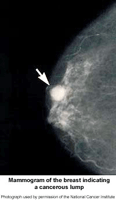

Picture of mammogram of the breast indicating a cancerous lump

A mammogram is an x-ray examination of the breast. It is used to detect and diagnose breast disease in women who either have breast problems such as a lump, pain, or nipple discharge, as well as for women who have no breast complaints.

Mammography cannot prove that an abnormal area is cancer, but if it raises a significant suspicion of cancer, tissue will be removed for a biopsy. Tissue may be removed by needle or open surgical biopsy and examined under a microscope to determine if it is cancer.